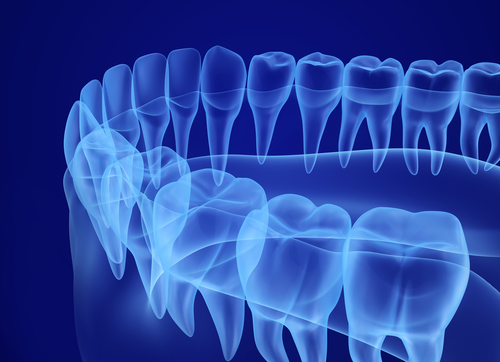

3D Imaging

Our advanced 3D imaging technology allows us to capture highly detailed, low-radiation scans that improve diagnostic accuracy and treatment planning. With this state-of-the-art system, we can evaluate complex anatomy, customize care, and reduce the number of visits needed for effective results.